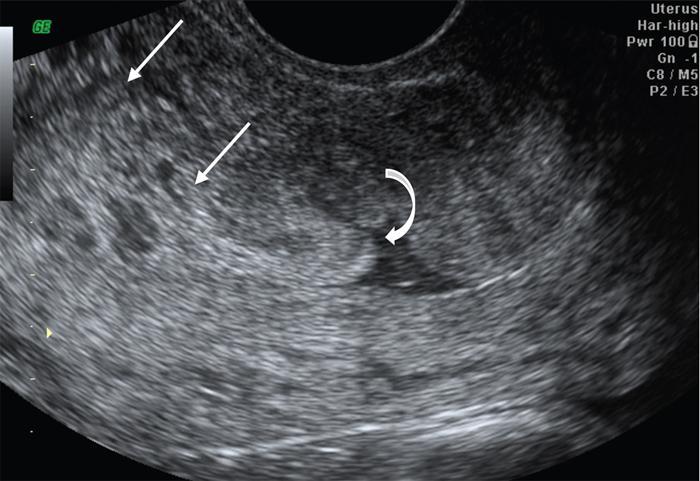

John De Lindsay, Sumathy, Vasumathy, Usha nandhini Ganeshan, N. Sundari ENDOMETRITIS Endometritis is defined as the inflammation of the uterine endometrial layer. Endometritis is frequently observed in the pregnant and postpartum population. Pelvic inflammatory disease (PID) and invasive gynaecological procedures are the most common causes of acute endometritis in nonobstetric population. Endometritis is the most complex asymptomatic and often presents with subclinical form of PID. Ultrasound may reveal minimal particulate endometrial fluid with mildly thickened endometrium showing increased vascularity. Computed tomography (CT) findings include a diffusely bulky uterus due by inflammation, mild fluid distension of endometrial cavity and striking endometrial enhancement in comparison to the adjacent myometrium due to mucosal hyperaemia. ‘Indistinct uterine border’ sign is observed in patients with endometritis, which is defined as the loss of distinction between the uterus and the adnexa. Since it is also observed in the cases of endometriosis or malignancy, it is a nonspecific sign. The age of the patient, clinical presentation, and the biopsy of endometrium helps in differentiating endometritis from other pathologies. UTERINE ARTERIOVENOUS MALFORMATION Uterine arteriovenous malformation (UAVM) is an abnormal connection between the arteries and the veins of the uterine myometrium without an intervening capillary bed. They were first reported by Dubreil and Loubat in 1926. They can be congenital or acquired. Even though UAVMs have varied presentation, uterine bleeding is the most common one. They often follow a pregnancy event. Episodic or occasionally torrential vaginal bleeding can occur. Congestive heart failure secondary to vascular steal can be a rare presentation due to a large UAVM. UAVM is most commonly an acquired condition. Pregnancy has a significant role in their pathogenesis. It is most commonly observed in reproductive age group. UAVMs are frequently observed in the postpartum period, few months after spontaneous miscarriage, surgical evacuation of uterus for miscarriage or medical termination of pregnancy. Infection, inflammation, retained products of conception (RPOC), gestational trophoblastic disease (GTD), gynaecologic malignancies, pelvic trauma and exposure to diethylstilboestrol can also lead to UAVMs. Few cases are also reported in young adolescent and postmenopausal females. UAVMs rarely are congenital and may be also associated with AVMs in other locations. Congenital AVMs Congenital AVMs have a central nidus with multiple feeding arteries and draining veins. In this condition, there is extension of the lesion beyond that uterus and multiple pelvic vessels other than uterine vessels draining into them. That cause of congenital AVMs are thought to be due to failure of embryological differentiation. With the progression of pregnancy, these vessels have the propensity to invade surrounding structures. Iatrogenic Acquired AVMs When the venous sinuses are incorporated into the scars of myometrium after the necrosis of chorionic villi, acquired malformations may arise. In contradiction to congenital AVMs, acquired AVMs multiple fistulous communication between the intramural arteries and the venous plexus. These AVMs may have either dual blood supply or a single supply from the uterine arteries and presents without nidus. Vaginal bleeding caused by pregnancy-related causes must be differentiated from UAVMs. Surgery/evacuation is the appropriate management for the former and the same is contraindicated in the UAVMs and hence an accurate definitive diagnosis is important. Grey-scale ultrasound findings are nonspecific and they are subtle heterogeneity of myometrium with multiple tubular or ‘spongy’ anechoic or hypoechoic areas. In spite of varied presentations such as an intramural uterine, endometrial or cervical mass-like lesions or prominent parametrial vessels, it has minimal mass effect. On colour Doppler, within the myometrium, a region of increased vascularity and most commonly with aliasing is seen. A group of vessels traversing the myometrium running perpendicular to and into the endometrium, from the arcuate vessels, can be seen. It is not specific, as they are also observed in RPOC, GTD, placental polyp and vascular endometrial neoplasm. In pulsed Doppler, multidirectional turbulent flow with intense vascularity can be seen with high peak velocity (mean peak systolic velocity [PSV] = 136 cm/s) and low resistance (mean resistance index = 0.3) flow. The arteries have low pulsatility while the draining veins are pulsatile and show high velocity flow. Magnetic resonance imaging (MRI) offers noninvasive confirmation of the diagnosis of UAVM. T1-weighted and T2-weighted images show multiple serpentine signal voids along the uterine wall, endometrial cavity and parametrium. Contrast-enhanced MR angiography shows intensely enhancing complex serpentine abnormal vessels with early venous return. Catheter angiography can be reserved only for women who require embolization of the AVM. The consent for both diagnostic angiography and therapeutic embolization should be obtained simultaneously to avoid repeat therapeutic procedures. Management of UAVM depends on: UAVM can be treated with medical therapy with hormones, uterine artery embolization or with definitive hysterectomy. Once the diagnosis of a UAVM is confirmed, the treatment option depends on the clinical condition of the patient. The size of the AVM bears no correlation to the need for embolization. Timmerman et al. found that AVMs having PSV of at or above 0.83 m/s, most often requires embolization. Also, the vascular malformation with PSV value below 0.39 m/s does not require embolization. Placental bed subinvolution, enhanced myometrial vascularity (EMV), molar pregnancy or RPOC are the other causes of uterine mass vascular malformations which usually has a mean PSV of 0.52 m/s and does not require embolization. Transcatheter targeted uterine artery embolization is indicated in selected cases, if bleeding persists to a degree that blood transfusions are required to maintain haemodynamic stability or multiple repeated acute hospitalizations. This is preferred over surgical management owing to its immediate minimally invasive and fertility sparing benefits. Gelfoam had been suggested earlier as the material of choice for embolization. Various other embolic materials like polyvinyl alcohol, Histoacryl glue, stainless steel coils, detachable balloons, and haemostatic gelatin are also used nowadays. Normal intrauterine pregnancies after embolization have been reported, proving that an adequate collateral blood supply can develop to support a full-term pregnancy. Gestational Trophoblastic Disease RPOC: Presence of endometrial pathology rather than myometrial origin. FIBROIDS Leiomyomas, also known as fibroids or myomas, are the most common gynaecologic neoplasms, occurring in 20%–30% of women of reproductive age. Symptomatic uterine fibroid accounts for about 30% of hysterectomies performed for women older than 18 years of age and 41% of hysterectomies performed for women from 44 to 64 years of age. Leiomyomas are the benign neoplasms made up of whorled fascicles of smooth muscle and fibrous connective attached to the uterine muscular wall. Even in the absence of true capsule, leiomyomas are well circumscribed and contains a pseudocapsule. Its size is variable, ranging from tiny microscopic to large tumours filling the abdomen. Most commonly, the uterine leiomyomas are seen in the myometrium of uterine corpus. However, it is also seen in the cervix (<5% of cases). On the basis of the location, uterine fibroids are classified as submucosal, intramural or subserosal. This classification is of clinical significance because the symptoms and treatment vary among these subtypes of leiomyomas. Submucosal myomas are further subclassified as 0, I and II depending on the percentage within the endometrial cavity. The first two categories can be removed hysteroscopically (Table 11.15.3.1). Pedunculated leiomyomas are attached to the uterus by a stalk and may be either intracavitary or exophytic (narrower than 50% of diameter of myoma). Rarely, a submucosal fibroid may grow pedunculated and extends into the cervical canal or vaginal canal and its prevalence is about 2.5%. Pedunculated subserosal leiomyomas may undergo torsion, resulting in infarction accompanied by pain. Lateral growth into broad ligament leads to intraligamentous leiomyoma (Table 11.15.3.1). Rarely, a pedunculated leiomyoma may become detached from the uterus (parasitic leiomyoma). Depending on the location, size and number of uterine fibroids, it has varied presentation. Symptoms caused by leiomyomas are classified into three different categories such as abnormal uterine bleeding, pelvic pressure and pain and reproductive dysfunction. Submucosal leiomyomas and intramural leiomyomas are often associated with menorrhagia (Table 11.15.3.1). Because of leiomyoma, uterus may be irregularly shaped and causes symptoms based on their locations. Anterior leiomyomas cause urinary symptoms, whereas the posterior leiomyomas cause constipation. Ureter may be compressed by broad ligament leiomyomas and presents as hydroureter or hydronephrosis. In case of degeneration or torsion of a pedunculated leiomyoma, acute pain may be the presentation. Leiomyomas are an infrequent primary cause of infertility. Malpresentation, pregnancy failures and dystocia are reported. Ultrasound is the first-line imaging modality because it is a cost-effective portable real-time examination that provides good anatomic detail. Leiomyomas appear as a well-defined round or oval hypoechoic solid mass. It is mostly associated with posterior shadowing possibly due to calcifications or interface of the margins of the leiomyoma with the normal myometrium. Degeneration or lipoleiomyoma can be suggested when there is internal echo-poor or hyperechoic foci, respectively. The presence of hypervascularity in a large solitary uterine mass can identify suspicious masses, such as a leiomyosarcoma (LMS). Another study found that there is an increased detection rate of uterine sarcomas while using a cut-off value of 41 cm/s. In the assessment of a uterus enlarged with multiple leiomyomas, ultrasound has FOV limitations. Likewise, it has limited role in the assessment of retroverted uteri, pedunculated subserosal myomas and concomitant adnexal processes. Little has been reported regarding sonographic changes after MR HIFU and uterine fibroid embolization (UFE). Differential diagnosis has been discussed in Table 11.15.3.2. Hyperechoic unlike a myomatous polyp which appears hypoechoic Heterogeneous endometrium with little mass effect Enlarged uterus and a deformed contour are the most common computed tomography (CT) findings. Even though CT is the primary modality for the staging of cancers, it has limitation of reduced contrast resolution for the assessment of focal myometrial masses, and associated with risk of ionizing radiation. Also, in delineating the zonal anatomy for accurate localization of leiomyomas and LMSs, CT is inferior to magnetic resonance imaging (MRI). More often dense or amorphous calcification is seen. Almost exclusively, on plain radiography or CT, these patterns of calcification favours the diagnosis of leiomyoma. Ring-like calcification at the margins of a leiomyoma is a rarely observed pattern, which represents the thrombosed veins. Positron emission tomography (PET)/CT is an ideal modality for the confirmation of malignancy and also helps in detection of metastasis and recurrence. In a small study of patients with histopathologically confirmed uterine sarcoma found that on comparing with the findings of MRI and ultrasound with power Doppler imaging, the results of fluorodeoxyglucose (FDG) PET examinations were 100% positive. However, it has limitations such as increased false-positive rate and reduced widespread availability. MRI appearance of leiomyomas: MRI is considered as the most accurate imaging technique for the detection and localization of leiomyomas. In determining the presence and location of leiomyomas in infertile women before myomectomy, MRI has been shown to be more accurate and sensitive than US or hysterosalpingography. Nondegenerated uterine leiomyomas usually has a typical MRI appearance of (Table 11.15.3.4) well-circumscribed masses with homogeneously decreased T2-weighted signal intensity. TABLE 11.15.3.3 Note: SI, signal intensity; ADC, apparent diffusion coefficient. Compared with that of normal smooth muscle myometrium. Degenerated leiomyomas have varied imaging appearances on T1-weighted, T2-weighted and contrast-enhanced images as described in Tables 11.15.3.4 and 11.15.3.5. Hyaline Oedema *Common *50% cases *Usually peripheral Cystic Myxoid Carneous, red, or UAE associated Calcific Leiomyoma variants (Tables 11.15.3.4 and 11.15.3.6): There are several, such as mitotically active, cellular and atypical leiomyomas, as well as smooth muscle tumours of uncertain malignant potential (STUMP). On histopathological examination, the nondegenerated fibroids are made up of goals of uniform smooth muscles with varied amounts of collagen. Cellular leiomyomas, which are composed of compact smooth muscles cells only with no collagen, will demonstrate increased T2-weighted signal intensity and homogeneous enhancement. There is a greater risk of recurrence in case of atypical leiomyomas and uterine STUMP. The patients who had undergone myomectomy and were found to have atypical leiomyoma, must be under surveillance with an annual pelvic ultrasound or MRI. Since the recurrences may presents as pelvic or abdominal masses or as pulmonary metastases, for all the patients with STUMP lesions, routine physical examinations, including pelvic examinations and the baseline CT of the chest, abdomen and the pelvis are recommended for every 6 months for 5 years and then annually thereafter. In addition, prompt re-exploration and staging is recommended for patients with STUMP who have undergone a morcellation myomectomy. An aggressive imaging surveillance is considered, when the disease is present. Atypical leiomyomas and STUMPs routinely express progestin receptors; however, because of the low recurrence rates, there is no role for adjuvant hormonal therapy. Atypical uterine masses can be treated surgically with hysterectomy or myomectomy. Histologic subtype Cellular leiomyoma Round or oval Single large lesion with absence of coexistent adenomyosis Responds to GnRH analogues Cured with surgery No need for follow-up Lipoleiomyoma Well defined: round or oval STUMP Round or oval Intense surveillance Note: SI, signal intensity; ADC, apparent diffusion coefficient; UAE, uterine artery embolization; STUMP, smooth muscle tumours of uncertain malignant potential. Being a benign neoplasm, fibroids usually have a pushing border and rounded edges. But, specific types of fibroids represent growth pattern variations, such as intravenous leiomyomatosis, metastasizing leiomyoma, diffuse leiomyomatosis and peritoneal disseminated leiomyomatosis. Retroperitoneal growth and parasitic growth are the other atypical growth patterns. Even cervical and vaginal leiomyomas may show growth pattern. It is important to note that adenomyosis and focal myometrial contraction can coexist and distinction is important at preprocedure imaging (Table 11.15.3.7).